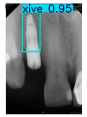

However, since the implant launched onto the market, dental treatment related to implant issues has become the everyday practice of dentists’ lives in clinics [10]. The design of the implants, from shape to surface coating, is different from brand to brand [11]. But it is inevitable to come into implant complications [12,13], such as screw fracture, healing abutment loss, etc., whether the clinician itself treats the implant or implant prosthesis. Different surface coatings [14,15] and threads of the implant design [16,17] may be easily identified in vitro. Moreover, once the implants are in vivo, the clinicians can only identify implant brands through radiography or the clinicians’ familiarity with the implant. If the clinicians are not familiar with the brands, then it is hard to tell which brand the implant is from in vivo. As the number of implant brands on the global market grows, it has become increasingly complex for clinicians to identify and familiarize themselves with all available implant systems accurately. 3i and Xive are two of the most widely used and clinically validated implant brands worldwide, with excellent long-term success rates [18] and reliable implant-abutment connection designs [19]. Therefore, we strategically focused on 3i and Xive implants in this study to ensure clinical relevance and practical significance. Concentrating on these two brands allows our model to address many real-world clinical cases and enhances its applicability in everyday dental practice. Clinicians will likely encounter both implant brands due to their widespread use in global dental clinics [20]. Moreover, as the implant’s screwdrivers differ from brand to brand, the identification of implant brands is very important to clinicians and patients. The marginal accuracy of the implant-abutment connection may vary due to misidentification and lead to unknown clinical problems [21,22]. The PA imaging results of two implant brands of different types at different resolutions (R) are shown in Figure 1. These two commonly used implant brands exhibit highly similar characteristics, with the most apparent difference being the variation in implant threading patterns. However, this distinction is not easily discernible for PA datasets.

Figure 1.

Imaging of two implant brands at different resolutions.